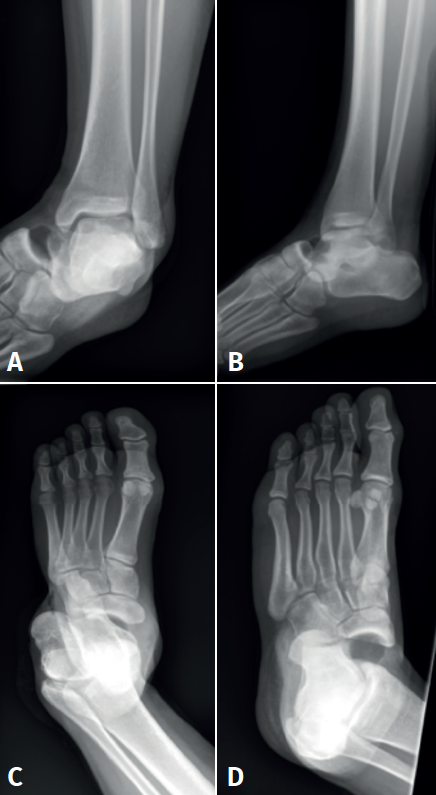

Se realizó reducción cerrada bajo anestesia (bloqueo raquídeo) y se comprobó la estabilidad mediante control fluoroscópico. Se realizó lavado abundante, sutura de la herida lateral y se inmovilizó con yeso cerrado almohadillado; posteriormente se realizaron radiografías lateral del tobillo y AP y oblicua del pie posreducción (Figura 2) y tomografía computarizada (TC) posreducción.

Figura 2. Radiografía lateral de tobillo (A) y anteroposterior (B) y oblicua (C) de pie  tras reducción cerrada e inmovilización con yeso.